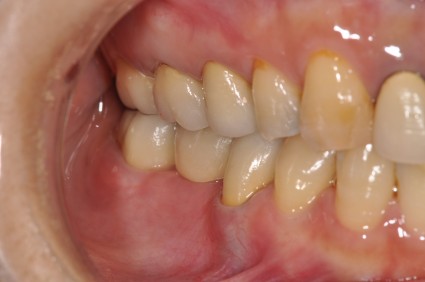

患者様は 右下の歯のない部分と かみ合わせの不調和を感じられ当院に受診されました。

上下のかみ合わせのバランスも一緒に整えた

インプラント治療と かみ合わせのバランスを整えることを 同時に 施術した患者さまです。